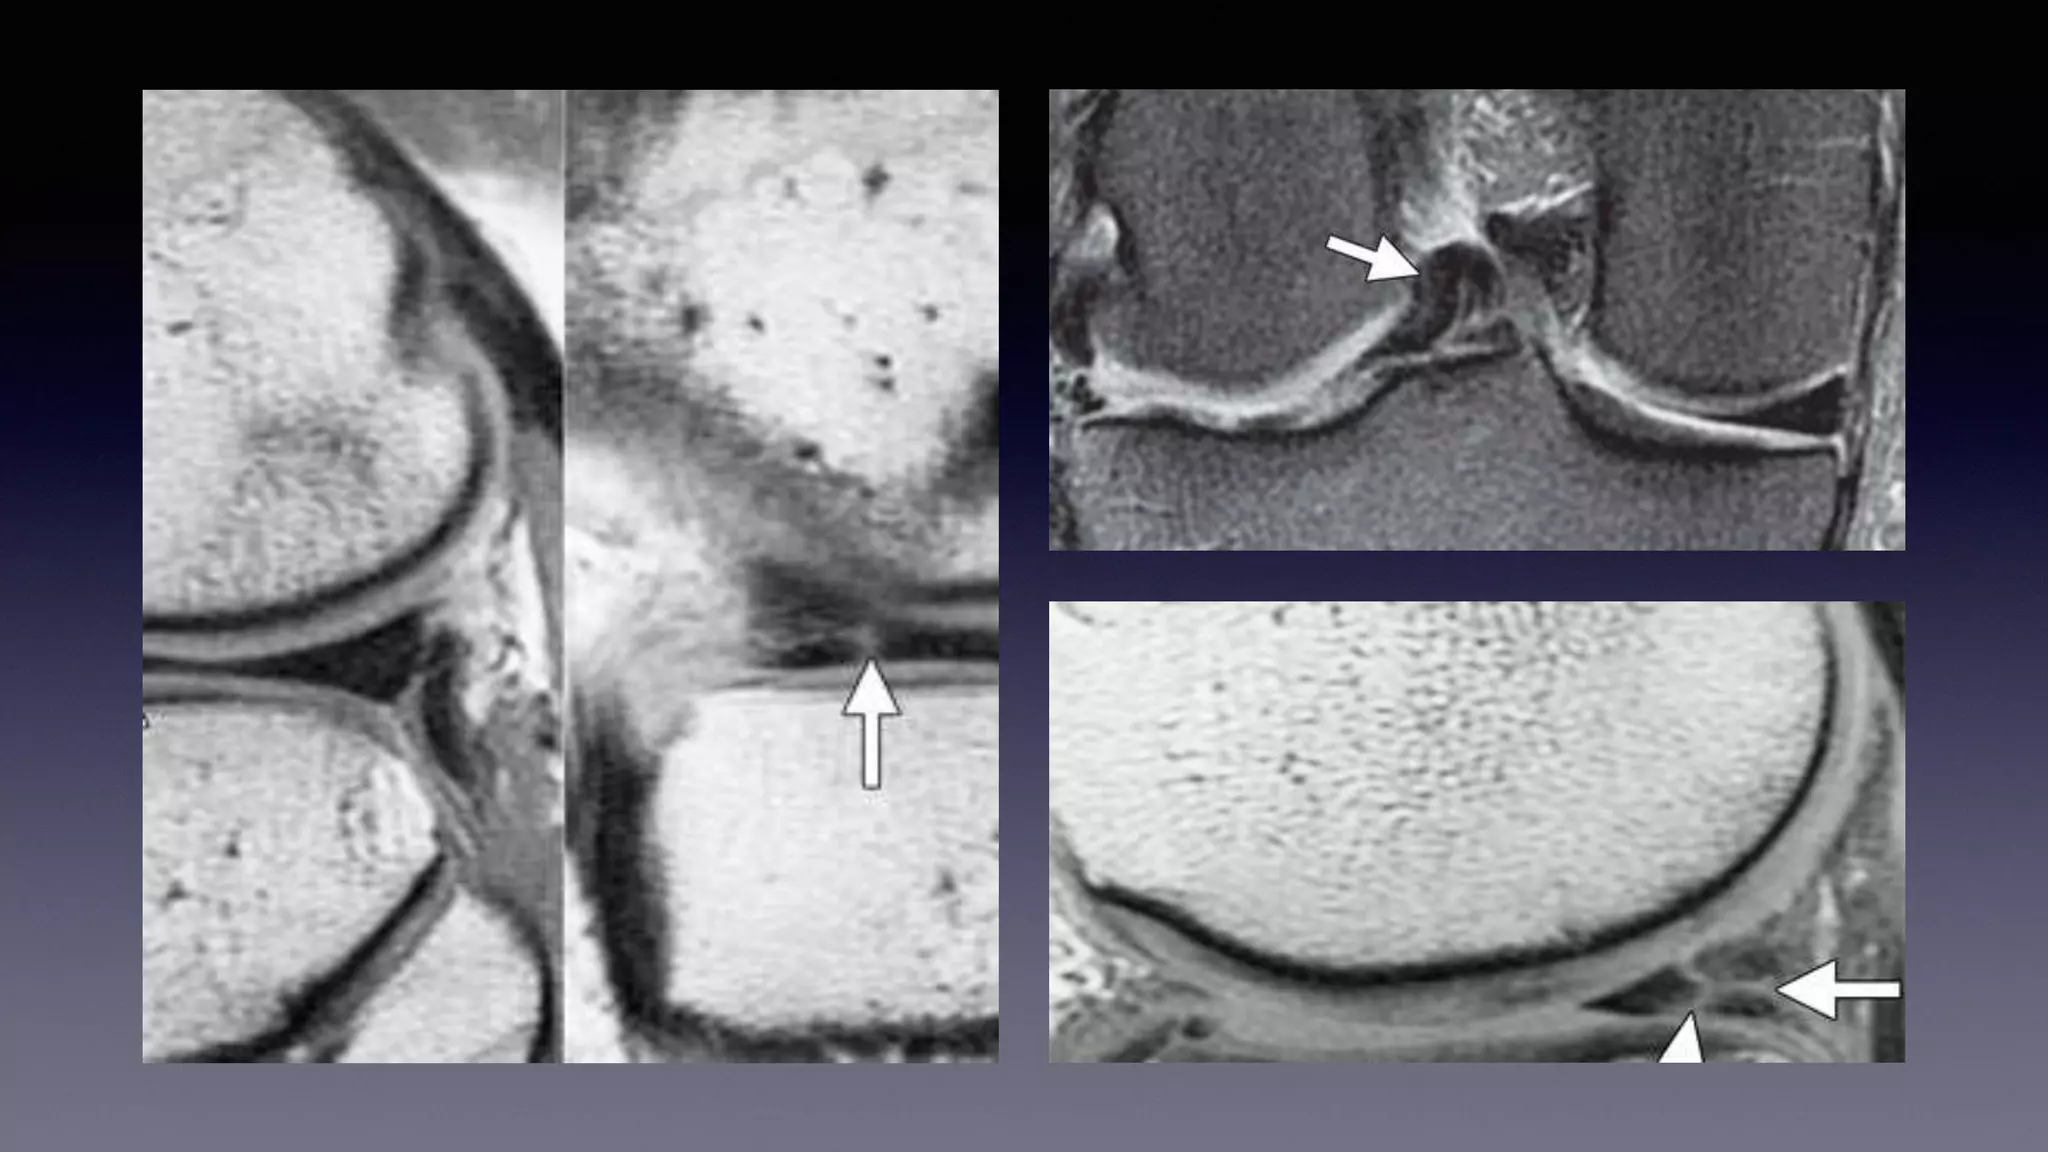

This document discusses using MRI to diagnose ligament injuries in the knee. It begins with an overview of MRI anatomy of the knee and expected pathology. It then discusses specific ligaments like the ACL, PCL, MCL and LCL. For the ACL, it shows images of acute tears, chronic tears and intrasubstance tears. It emphasizes knowing the knee anatomy well and correlating any abnormalities seen with clinical findings in order to apply the appropriate treatment.